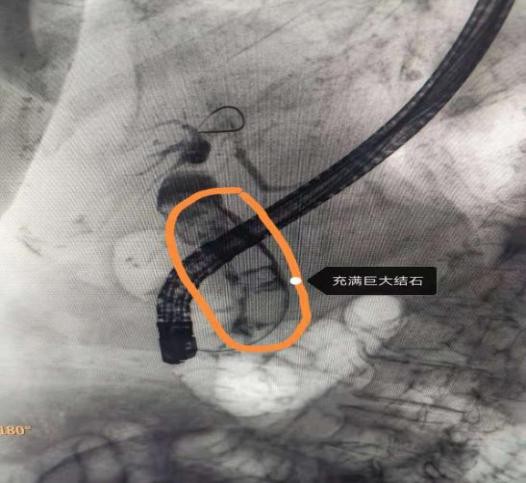

周阿姨入院后,胆道核磁共振检查提示她的胆总管内充满巨大结石,最大结石直径2.5cm,如果再次更换支架,有支架再次梗阻、移位和脱落的可能,反复住院时间长。如果行传统“胆总管切开取石+T管引流术”,对患者的创伤较大,术后容易出现并发症。

手术当日由史立军教授、李雯和于琪在消化内镜中心开展,术中可见原有胆管内支架已经梗阻失去引流作用,拔出支架后,选择胆管插管,导丝顺利进入胆管,造影可见胆管内充满巨大结石,最大结石约2.5cm。以扩张球囊将乳头开口扩张至1.0cm,乳头开口无活动性出血,而后插入数字胆道镜,可见胆管内巨大结石,而后经数字胆道镜插入激光光纤进行碎石,巨大结石被逐一击碎,而后用网篮将碎石取净,置入鼻胆管。术后患者无并发症,无创伤,鼻胆管造影无结石残留。